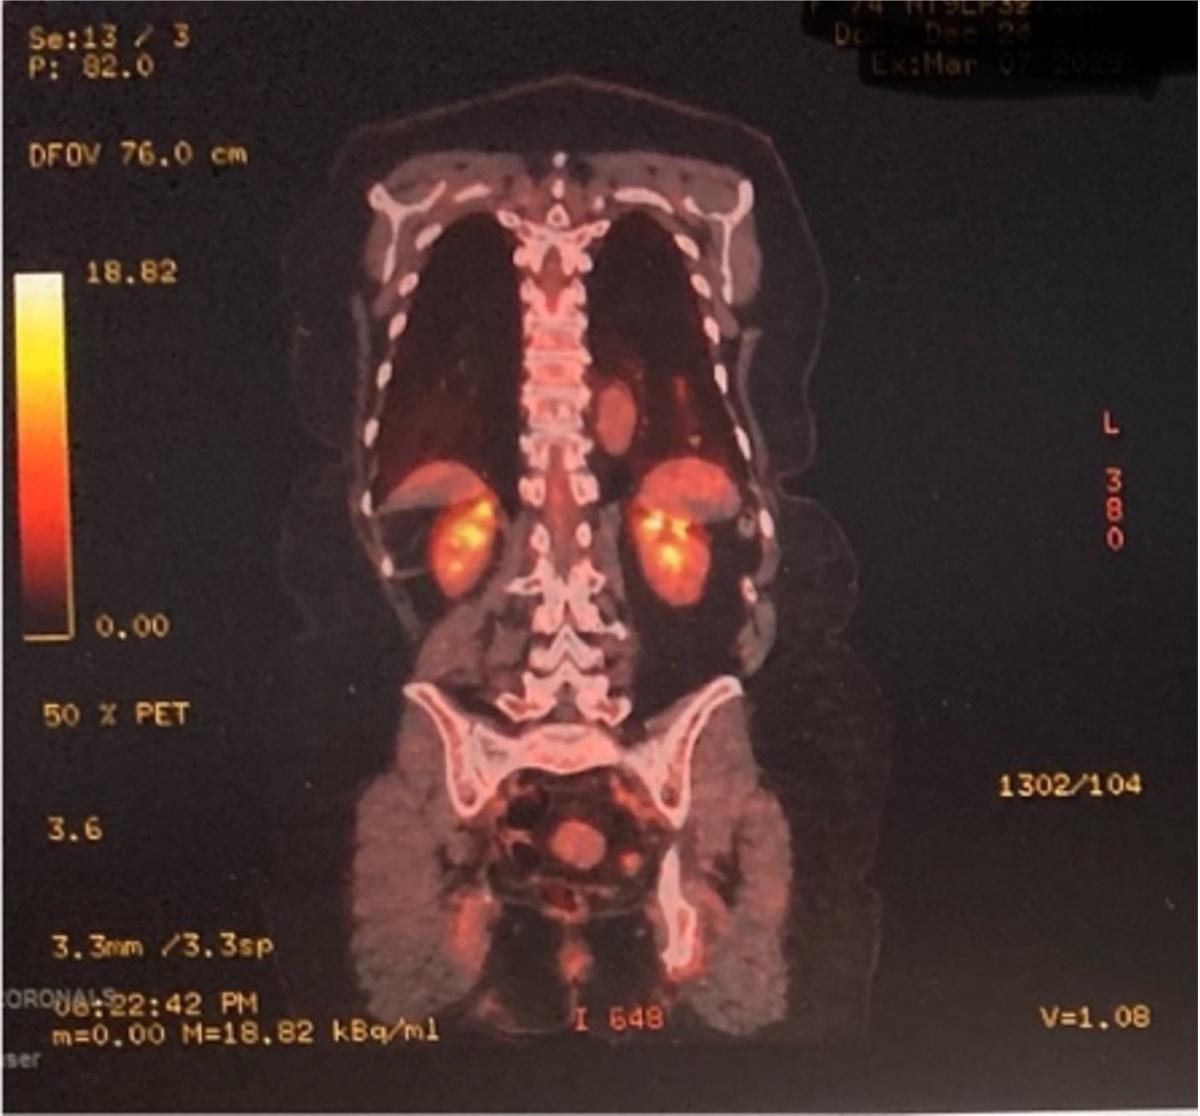

The patient underwent positron emission tomography (PET)/CT imaging that showed a fluorodeoxyglucose-avid lesion in the right upper lobe, yielding a Herder score of 91.7 percent, suggesting a very high likelihood of malignancy (Figures 3, 4). Following a multidisciplinary team discussion, the patient was subsequently recommended for a robotic-assisted segmental resection of the left S8 segment. This procedure was performed using a robotic system.

Figure 3: An image of the axial positron emission tomography (PET)/CT scan.

Figure 4: An image of the PET/CT coronal scan.

The PET/CT imaging showed a fluorodeoxyglucose-avid lesion in the left lower lobe and a Herder score of 91.7 percent (Figure 3).